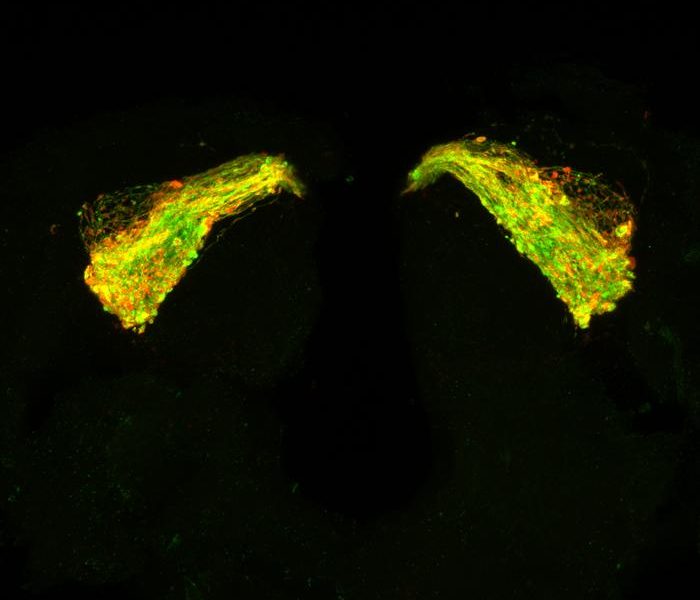

To understand what was happening, Southampton’s scientists looked deep into the brains of the fruit flies.

Prof Mudher said: “When we didn’t feed the flies with the peptide inhibitor, they had lots of the pathogenic fibrils, which group together to make up a tangle. But when we fed them with the drug, the pathogenic fibrils decreased significantly in quantity.”

Image: University of Southampton